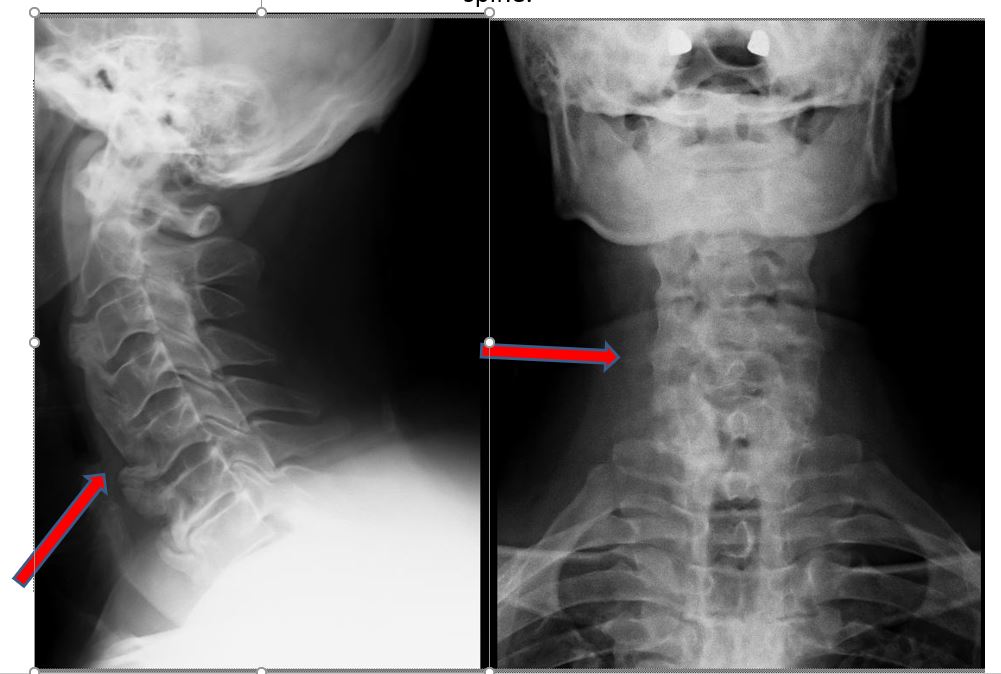

“Kur I.K erdhi te ne, veç të tjerash, kishte humbje të ekuilibrit gjatë ecjes, dhembje në të katër gjymtyrët, mpirje sidomos në këmbë (e djathta më shumë) dhe inkontinencë urinare. Rezonanca magnetike zbuloi një shtypje të fortë të palcës kurrizore në vertebrat C6-7 dhe C7-T1 të qafës. Ai gjithashtu kishte hiperostozis të segmentit cervikal të qafës gjë që i kishte bllokuar lëvizjen në të gjitha nyjet e saj. Sinjalet e shtyllës kurrizore kishin ndryshuar dhe nëse nuk do të operohej në kohë, do të ishte paralizuar plotësisht në të dyja këmbët dhe pjesërisht në të dyja duart”, tregon Prof. Dr. Kamil Cagri Kose.

Kirurgu i talentuar dhe me shumë eksperiencë tregon detajet e operacionit delikat: “Kryem korpektomi në vertebrën C7 dhe u hoq kocka e ngjeshur si dhe struktura të diskut. Gjithashtu u vendos një mbështetëse prej titani për të zgjidhur problemin dhe për të fiksuar segmentin në mënyrë që situata të mos përsëritet më”.